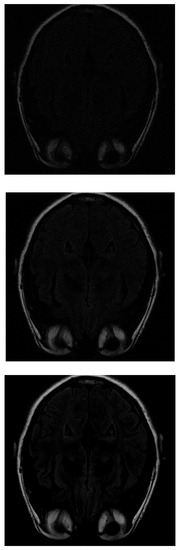

If IHTA is used for the reconstruction, more noise is detected on the inside of the head (where the white matter should be) with 30% of the initial signal values (Figure 7 top). With 70% of measurements (Figure 7 middle), an image similar to the same case was obtained with ISTA, but the target has more intense signals, which allows to distinguish better. The resolution increases as more data are added. However, when 100% of the data is reached (Figure 7 bottom), the white matter is not detected, it appears black.

Figure 7. Reconstruction of the image in Figure 3 using IHTA with 30 % (top), 70 % (middle) and 100 % (bottom) of taken measurements.

Mathematics 11 03573 g007